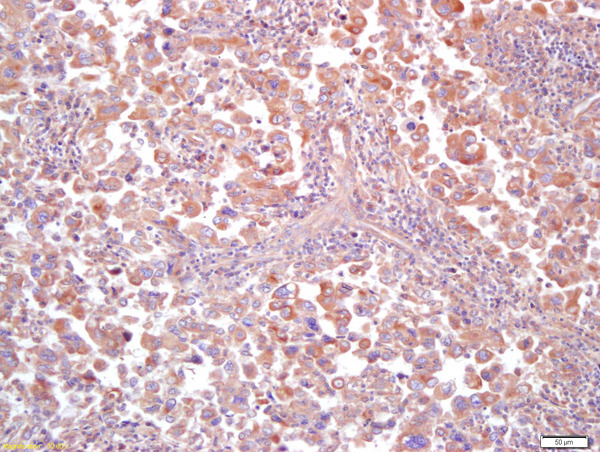

- Main image

- Experimental details

- Formalin-fixed and paraffin embedded human lung carcinoma labeled with Anti MT-ND5Polyclonal Antibody (bs-3952R), Unconjugated at 1:200, followed by conjugation to the secondary antibody and DAB staining

- Sample type

- Human

- Other comments

- Lung